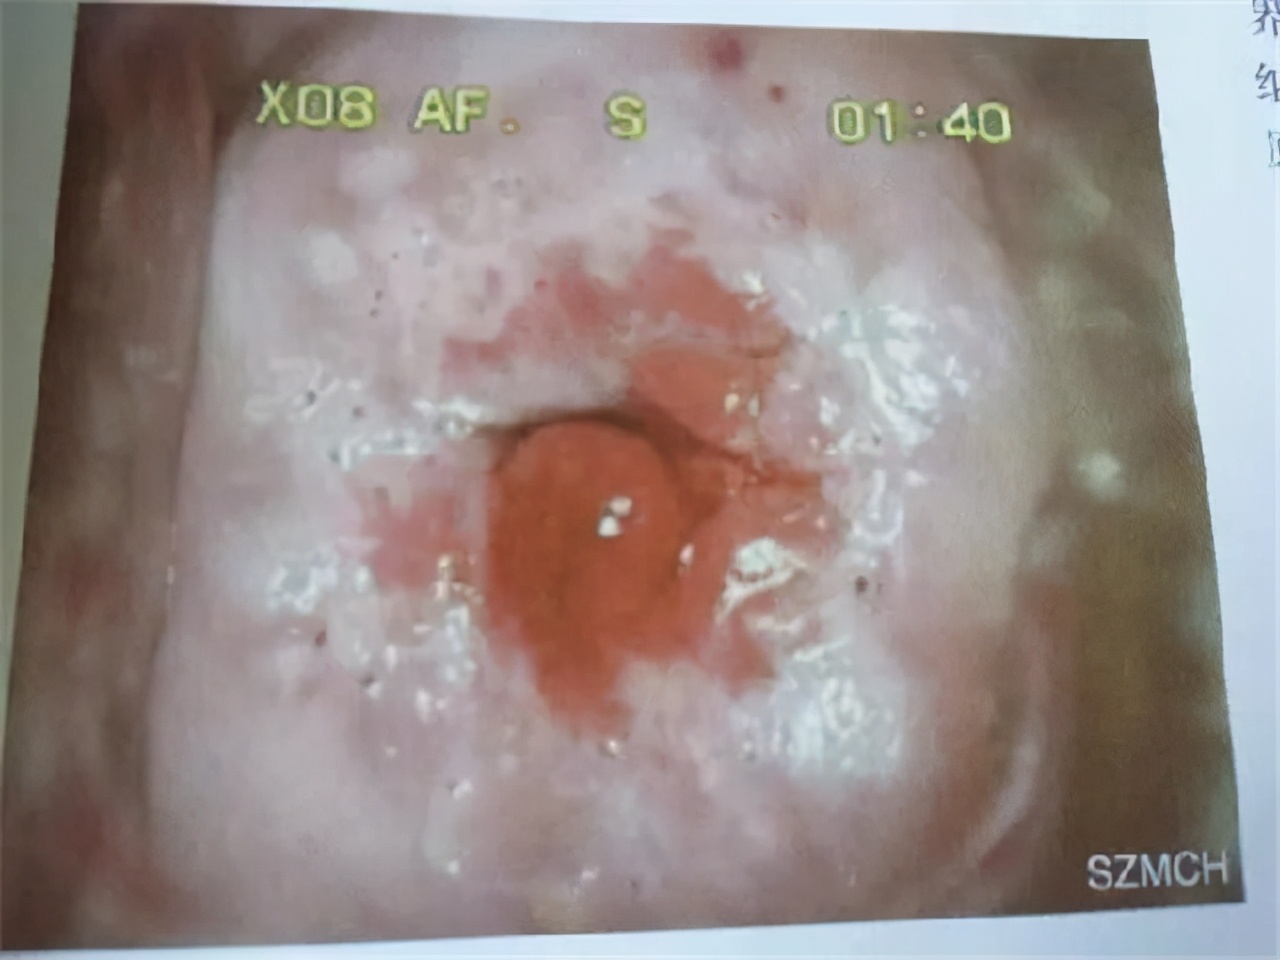

● 中期:宫颈癌变

患者45岁,宫颈癌变前期,宫颈口血管扩张充血,宫颈红肿,属于宫颈癌变中期发展阶段。患者时常感觉 腹部疼痛,月经推迟 的现象。通常宫颈癌发展到中期,身体会有一系列的不良反应,值得我们提高警惕。中期宫颈癌治疗以药物治疗为主,药力杀死癌细胞,抑制增长扩散,同时提高机体免疫活力,让病情得到缓解, 存活期在5-8年。